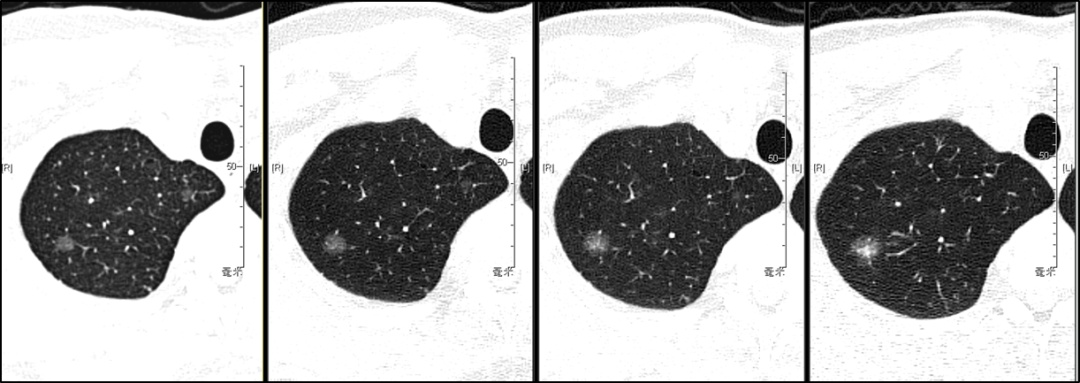

(4)假性收缩——潜伏隐藏的隐患

另外也有少部分结节,尤其是磨玻璃结节,随着时间推移,结节中心的细胞成分增多、变密,而周围的磨玻璃影却看似减少或消散,在CT影像上就呈现出结节整体“缩小”的假象。但这并非好转,反而可能是结节进展的危险信号。

此外,特别要强调的是,体检报告上描述的肺结节大小很大程度上受到检测仪器、摄片精度、测量选取截面及直径及被检者拍片时的配合情况等多方面因素等影响。因此,前后体检报告上结节大小几毫米的差异并不一定能反映真实情况。看到结节较前一次略有增大,不必太过惊慌。